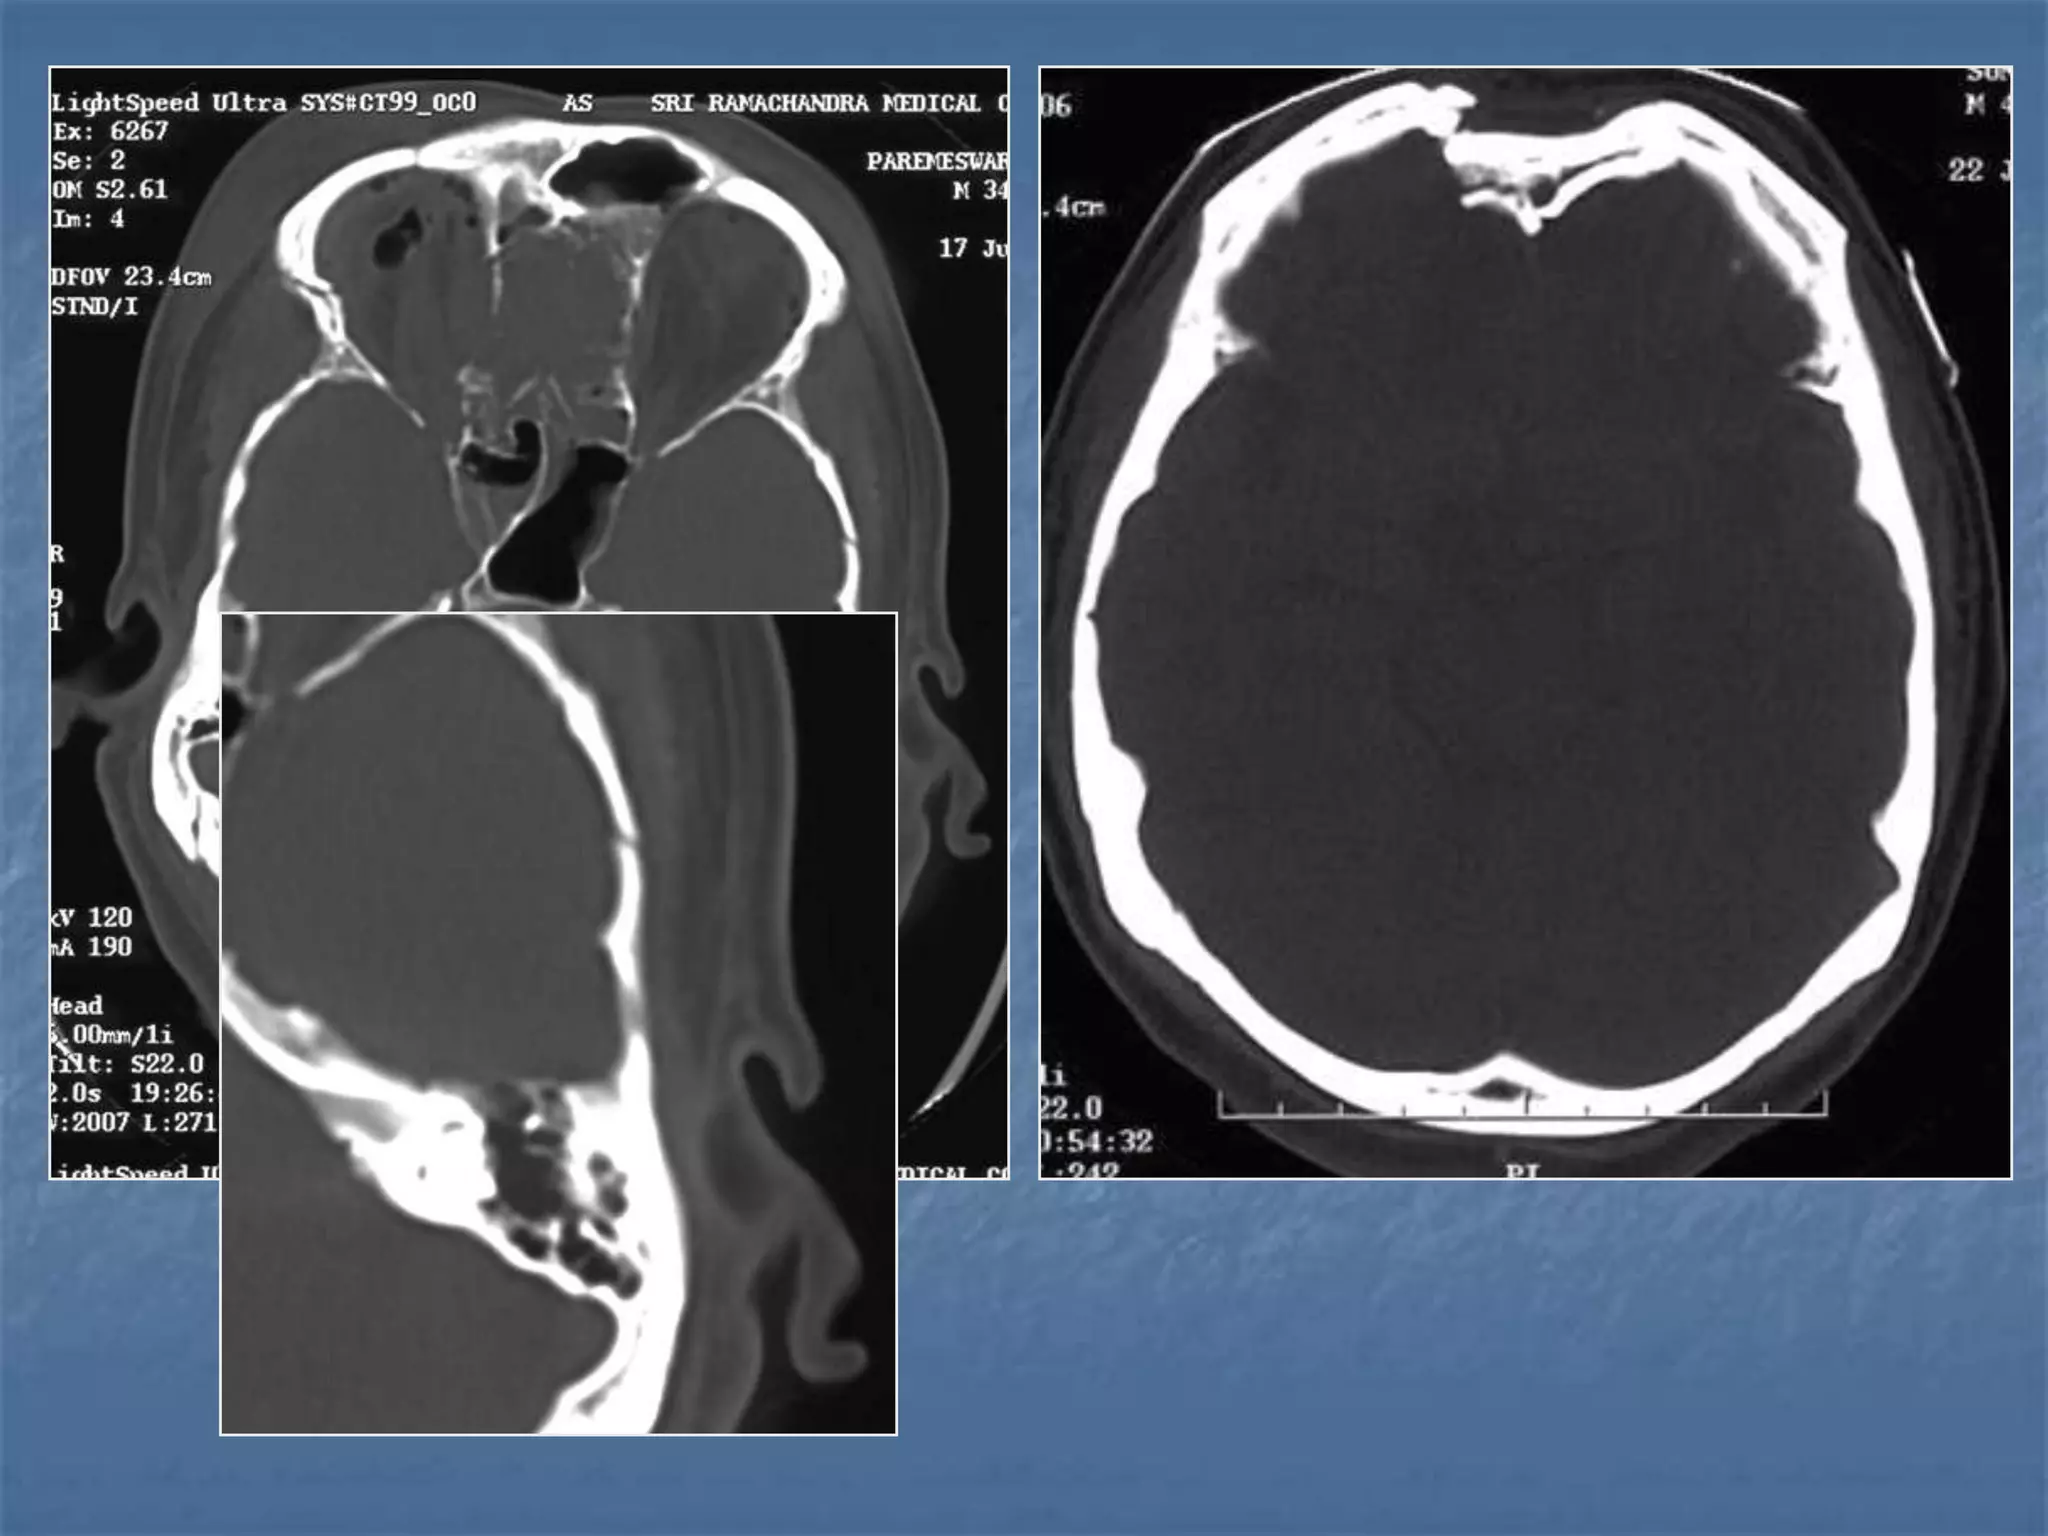

Epidural Hematoma

 An epidural hematoma is usually associated with a skull

fracture. It often occurs when an impact fractures the

calvarium. The fractured bone lacerates a dural artery or a

venous sinus. The blood from the ruptured vessel collects

between the skull and dura. On CT, the hematoma forms a

hyperdense biconvex mass. It is usually uniformly high

density but may contain hypodense foci due to active

bleeding. Since an epidural hematoma is extradural it can

cross the dural reflections unlike a subdural hematoma.

However an epidural hematoma usually does not cross

suture lines where the dura tightly adheres to the adjacent

skull

Skull Fractures

 Skull fractures are categorized as linear or depressed,

depending on whether the fracture fragments are

depressed below the surface of the skull. Linear

fractures are more common. The bone windows must

be examined carefully. A skull fracture is most clinically

significant if the paranasal sinus or skull base is

involved. Fractures must be distinguished from sutures

that occur in anatomical locations (sagittal, coronal,

lambdoidal) and venous channels. Sutures have

undulating margins both sutures and venous channels

have sclerotic margins. Venous channels have

undulating sides. Depressed fractures are characterized

by inward displacement of fracture fragments.